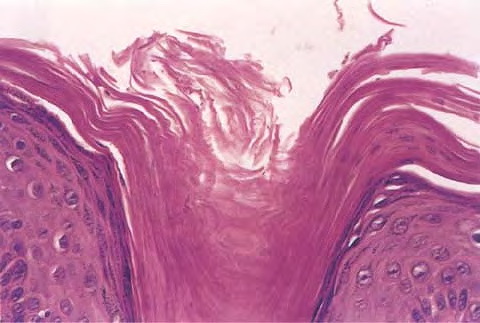

Pilar cyst = كيسة الشعر Pilar Cyst Pilar or trichilemmal cysts are clinically indistinguishable from epidermal cysts but differ from them in frequency and distribution. They are less common than epidermal cysts, constituting only about 25% of the combined material; about 90% occur on the scalp . Pilar cysts often show an autosomal dominant inheritance […]